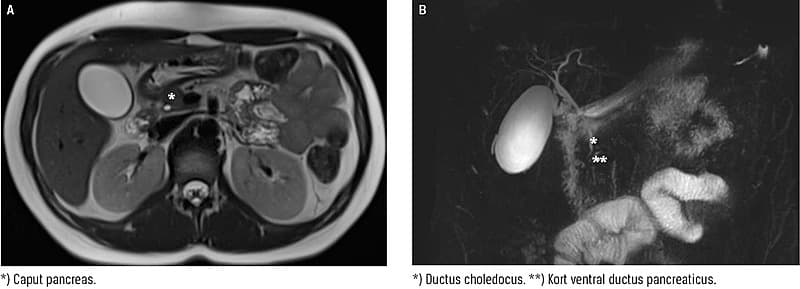

En abdominal ultralydskanning viste normale forhold af lever og galdeblære uden synlige konkrementer med insufficient indblik til pancreas. En efterfølgende MR-kolangiopankreatikografi afkræftede, at der var sten i de ekstrahepatiske galdeveje (B), men der var komplet agenesi af dorsale pancreas (A) (ADP).

ADP blev tolket som et incidentialt fund.